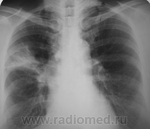

Пневмония?

Мужчина, около 35, жалобы на слабость, ознобы, повышение температуры до 37,5.

Думаю, не стоит грузить терапевтов с возможной пневмонией. ТМГ и к фтизиатрам.

Согласна, для пневмонии температура не высока. А потом-то ли наложение теней, то ли правда-видится мелкая полость?

Ничего особо не вижу, только левый корень некрасивый и за левой ключицей какое-то подобие очагов

Да, "менежится" на уровне левой ключицы инфильтрат.

Под левой ключицей облаковидный инфильтрат с подозрением на полость,отправить к фтизиатру

Да нет))), высокий, худой, вид несколько изможденный...видно - что болен. Несколько лет назад был правосторонний плеврит, нынешние изменения справа внизу - его последствия.

Ещё за тенью сердца что-то лишнее чернеется).